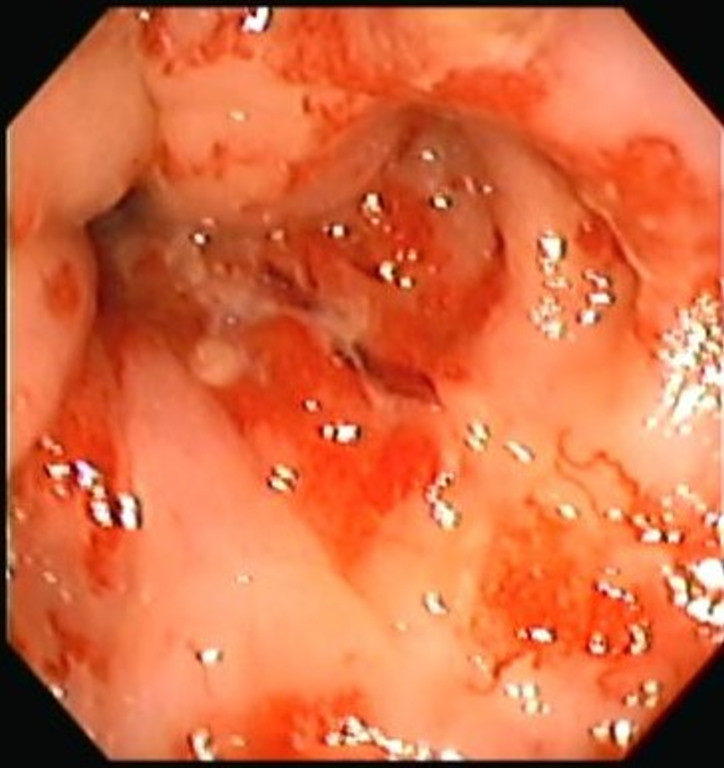

Proctitis

Envíado por Dr. Carlos Ernesto Arévalo